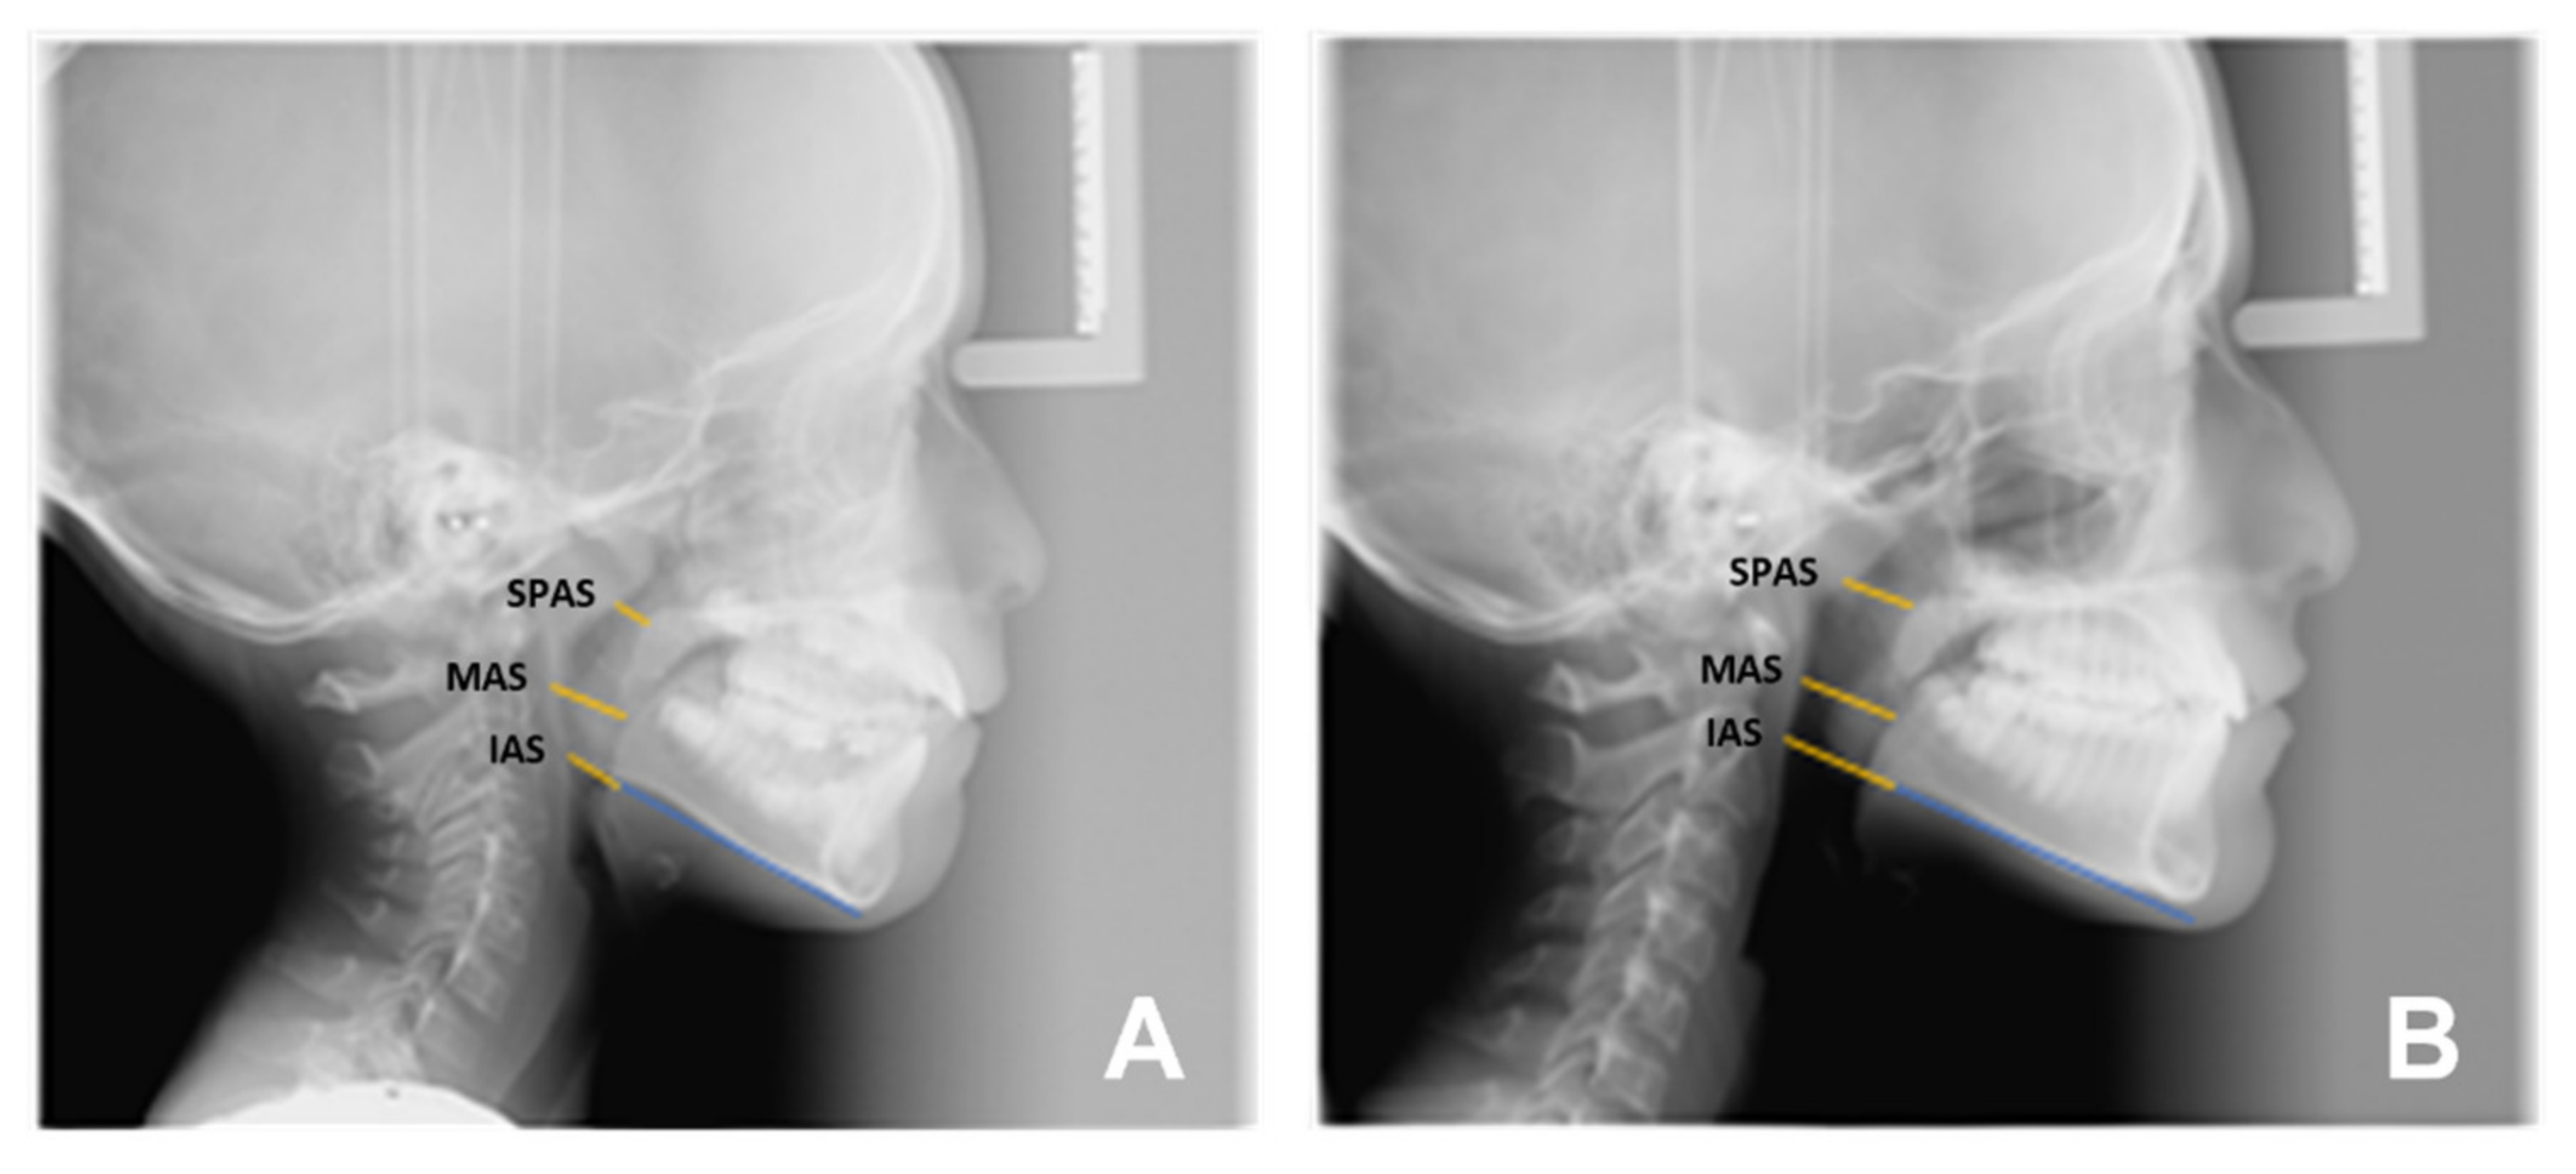

- Airways outcomes: significant changes were found in the width of the upper airways, SPAS (2.21 mm, p = 0.0099), while the improvement in the middle and lower pharyngeal space was not significant, i.e., MAS (1.41 mm p = 0.0786) and IAS (1.64 mm p = 0.1342).

| Sagittal plane analysis: SNA (angle comprised between Sella–Nasion and Nasion point A segments) SNB (angle comprised between Sella–Nasion and Nasion point B segments) ANB (angle comprised between Nasion point A and Nasion point B segments) Vertical plane analysis: Sna-Snp^Go-Gn (intermaxillary angle, angle comprised between the bispinal plane and the mandibular plane) S-N^Go-Gn (mandibular angle, angle comprised between the Sella–Nasion segment and the mandibular plane) PFH/AFH (posterior facial height and anterior facial height ratio) Growth predictors: N-S-Ar (saddle angle comprised between Nasion–Sella and Sella–Articular segments) S-Ar-Go (articular angle comprised between Sella–Articular and Articular–Gonion segments) Ar-Go-Me (gonial angle comprised between Articular–Gonion and Gonion–Menton segments) Ar-Go-N (upper gonial angle comprised between Articular–Gonion and Gonion–Nasion segments) N-Go-Me (lower gonial angle comprised between Nasion–Gonion and Gonion–Menton) Dental analysis: Is:NA (maxillary incisor distance) Ii:NB (mandibular incisor distance) OVJ (overjet) OVB (overbite) IsIi: interincisal angle (angle between the major axis of the upper and lower incisors). Upper airway space analysis: SPAS: superior posterior airway space (distance between the soft palate and the posterior wall of the nasopharynx measured along a line parallel to Gonion–Menton (Go–Me) plane) MAS: medium airway space (distance between the lower tip of the soft palate and the posterior wall of the oropharynx measured on a line parallel to Go–Me plane) IAS Inferior Airway Space (distance between the lingual base along the mandibular Go-Me plane and the posterior wall of the pharynx) Mandible measurements Ar-Go (ramus height measured on Articular-Gonion segment) Go-Me (corpus length measured on Gonion-Menton) |

| SPAS | 2.21 | 2.9040 | 0.0099 * |

| MAS | 1.41 | 1.8718 | 0.0786 |

| IAS | 1.64 | 1.5728 | 0.1342 |